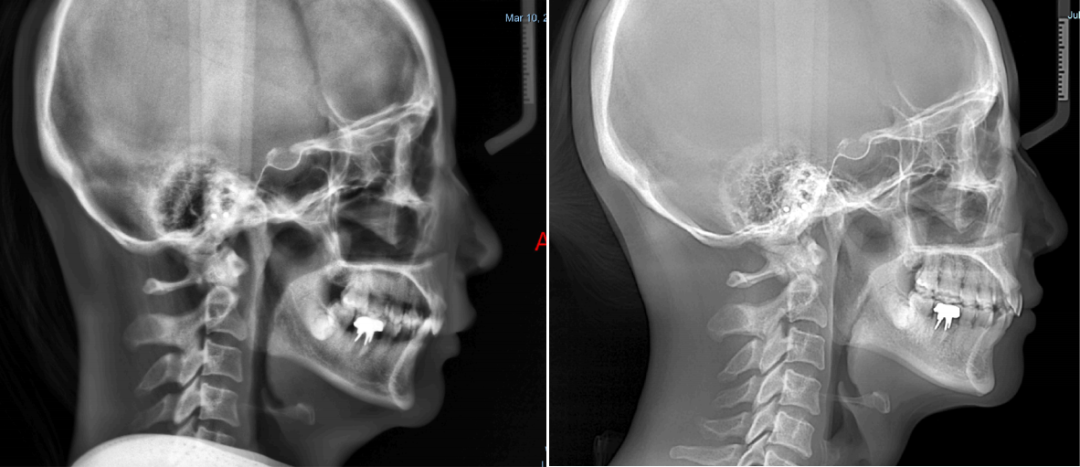

整个牙齿矫正过程,女士配合良好,从牙齿、咬合、面型上看,都得到理想的变化,可以看到上下前牙排齐,牙弓形态对称,面型维持良好,兼顾了美观和健康。

通过牙片资料可以看到女士是闭锁性深覆合,上牙几乎把下牙完全盖住,整个咬合关系并不是很理想,从侧貌看,她的下嘴唇相对靠后,下巴有点后缩,颏唇沟很深。